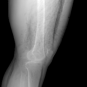

In this section, we provide qualitative and quantitative results of the two proposed diffusion-based methods and compare them with the baseline U-Net model. The first column of Fig. 3 showcases six randomly selected conditions: (a0)-(c0) show contour segmentations, and (d0)-(f0) denote segmentations containing contour and bones. In Fig. 3 (a1)-(f1), the images generated by U-Net contain blurred fine details in locations where bones overlap, despite maintaining the given shape, as highlighted by the red circle. In contrast, the results from CSM appear more realistic than the U-Net. However, their quality decreases with introduced constraints, as indicated by the red arrow in Fig. 3 (d2) and (f2). The results from CTM not only achieve nearly the same level of fineness as the labels but also provide reasonable results with respect to the given conditions as illustrated in the fourth column.

Table I summarizes the quantitative results averaged across all testing data. The evaluation metrics include mean absolute error (MAE) and peak signal-to-noise ratio (PSNR). We observed that CTM performs substantially better than U-Net and CSM under both segmentation-based conditions, and CSM performs worse than the U-Net.

Unlike the U-Net which learns a mapping function between input and output, the diffusion models can implicitly capture the underlying data distribution from the training data and then sample it, preventing the loss of fine details on the pixel level. However, in CSM, conditions are incorporated only at the first sampling step while being perturbed, which results in imprecise conditional information. Instead, CTM provides an estimated score function of the conditional distribution for each sampling step, accommodating both reliability and realism. Nonetheless, presently generated X-ray images only encompass independent 2D conditional information, which may introduce geometric inconsistencies between a set of projections. Future research will focus on modeling 3D probabilistic distributions with the provided 2D conditions to enable CT reconstruction from the generated projections. In addition, clinical datasets will also be incorporated.